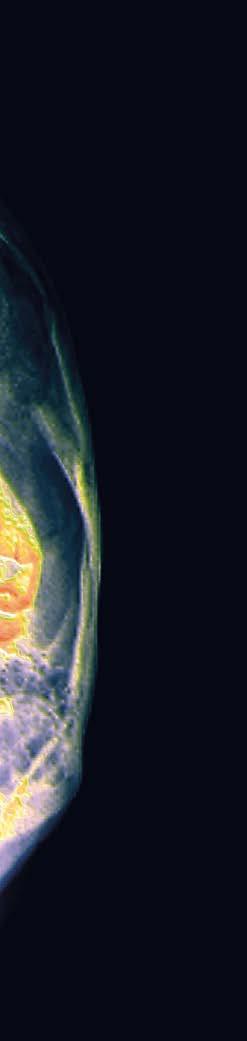

La glande mammaire est divisée en 15 à 20 sections que l’on appelle lobes, composés eux-mêmes de lobules.

Les seins sont constitués de graisse, de tissus conjonctifs, de glandes – les lobules – qui produisent du lait et de canaux galactophores (amenant le lait des glandes jusqu’au mamelon). Sensible car dotée de beaucoup de fibres nerveuses, la poitrine constitue également une zone érogène secondaire, plus ou moins investie selon les personnes et les cultures.

Développement durant la puberté Jusqu’à la puberté, les garçons et les filles ont des glandes mammaires, des mamelons et des aréoles similaires. Chez les filles, les seins se développent – à partir de 10 ou 11 ans – sous l’effet des œstrogènes –et atteignent leur taille adulte vers 17 ans. Leurs dimensions et leurs formes sont variées, de même que celles du mamelon et de l’aréole. Ces éléments n’ont aucune influence sur la santé ou la capacité à allai ter. Une poitrine trop volumineuse, aussi appelée hypertrophie mammaire, peut causer des douleurs dorsales et des difficultés lors d’activités physiques. Il est alors pos sible de pratiquer une réduction des seins.

Symbole de la féminité, le sein possède la particularité d’être grandement influencé au cours de la vie par les hormones. Son fonctionnement est aussi fascinant que sa taille et ses formes sont diverses. Ces dernières ne jouent aucun rôle sur la santé ou la capacité d’allaiter.

En Suisse, le cancer du sein est le cancer le plus répandu chez les femmes. En cause, des cellules glandulaires qui ont subi des modi fications pour diverses raisons. Certains cancers du sein sont directement influencés par les hormones féminines. Toutefois, dans la plupart des cas, l’origine de la maladie est multifactorielle.

Les thérapies contre le cancer ont beaucoup progressé ces vingt dernières années, ciblant plus spécifiquement certaines particula rités des différents types de tu meurs. Plus le cancer est détecté tôt, plus les chances de guérison sont grandes. Une mammographie tous les deux ans entre 50 et 74 ans, comme le préconise le programme établi par la Fondation genevoise pour le dépistage du cancer, ainsi que des contrôles gynécologiques annuels, demeurent primordiaux. L’auto-observation – il faudrait consulter lorsqu’une modification du sein ou du mamelon est consta tée – est aussi recommandée.

Parmi les autres maladies du sein, il faut mentionner les kystes ou les fibroadénomes, qui sont des affections bénignes, mais qui néces sitent parfois une intervention chirurgicale. Des mastites sur viennent lorsque le tissu mammaire s’enflamme suite à une infection. Elles sont courantes durant les premières semaines d’allaitement.

La ménopause représente une étape importante du cycle de vie des seins. Lorsque la production d’œstrogènes chute, la glande mammaire s’atrophie. Les seins, qui perdent alors leur capacité d’allaiter, se composent ensuite essentiellement de graisse.